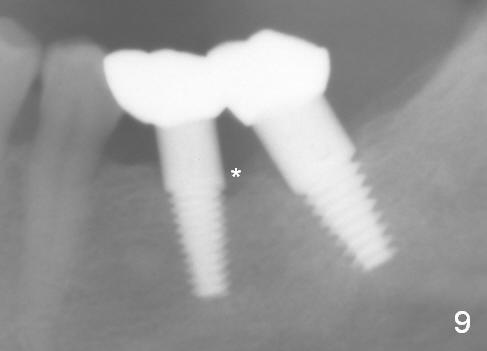

There is no bone loss around the implants 3 months postop (Fig.8). Crowns are delivered 5 months postop and have been in function for 3 months now. There is no gingival recession around the crowns. Panoramic X-ray is taken 1.5 years postop (1 year 1 month post cementation, Fig.9); there is mild bone resorption distal to #19 implant (*).